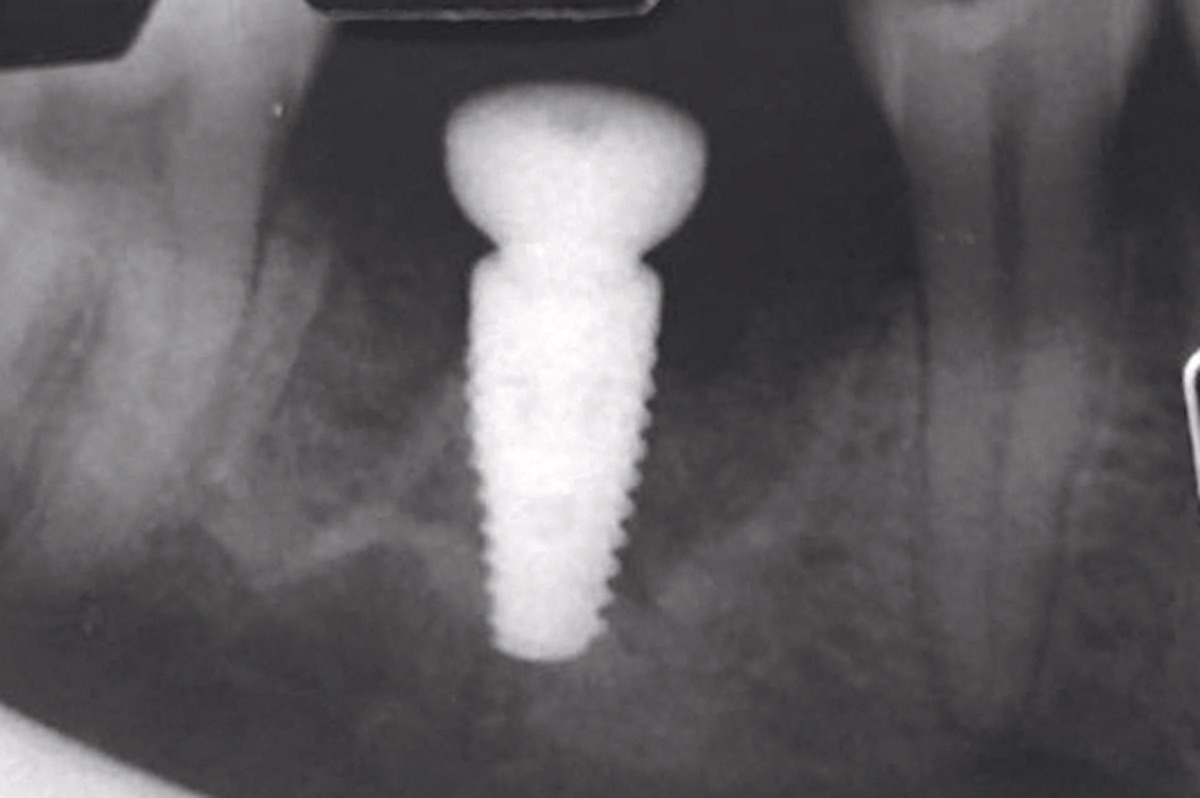

Pre-operative OPG, teeth 24, 25, and 26 planned for extraction